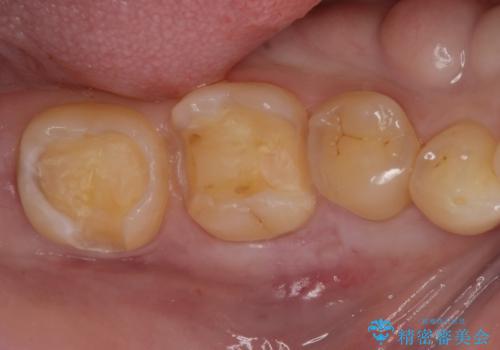

セラミックインレー。

- セラミック治療希望の患者様です。

古い樹脂の材料をとりe-maxの詰め物で治療を行いました。

適合の良い詰め物が入りました。